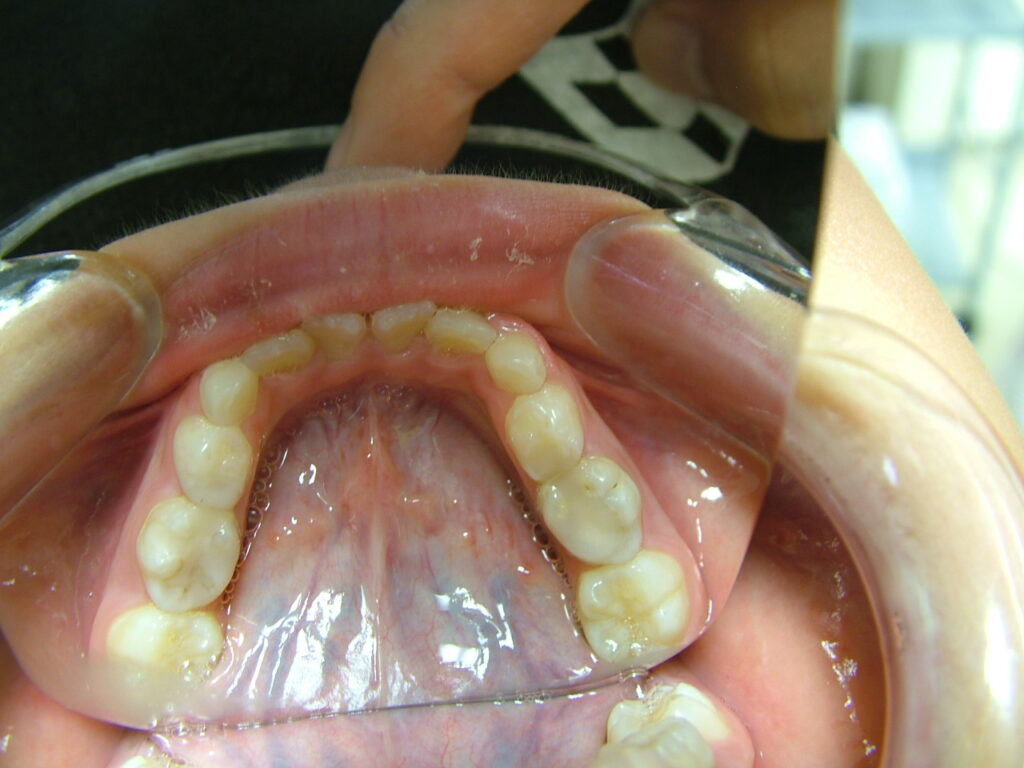

治療前

- 診断:1級咬合、左偏位、下永久歯(犬歯)萌出スペース不足

- 治療方針:非抜歯で行う。虫歯予防(フッ素)、歯磨き指導、舌位の改善、上下拡大床+補助断線→マウスピース矯正→下親知らずの抜歯、保定→メンテナンス